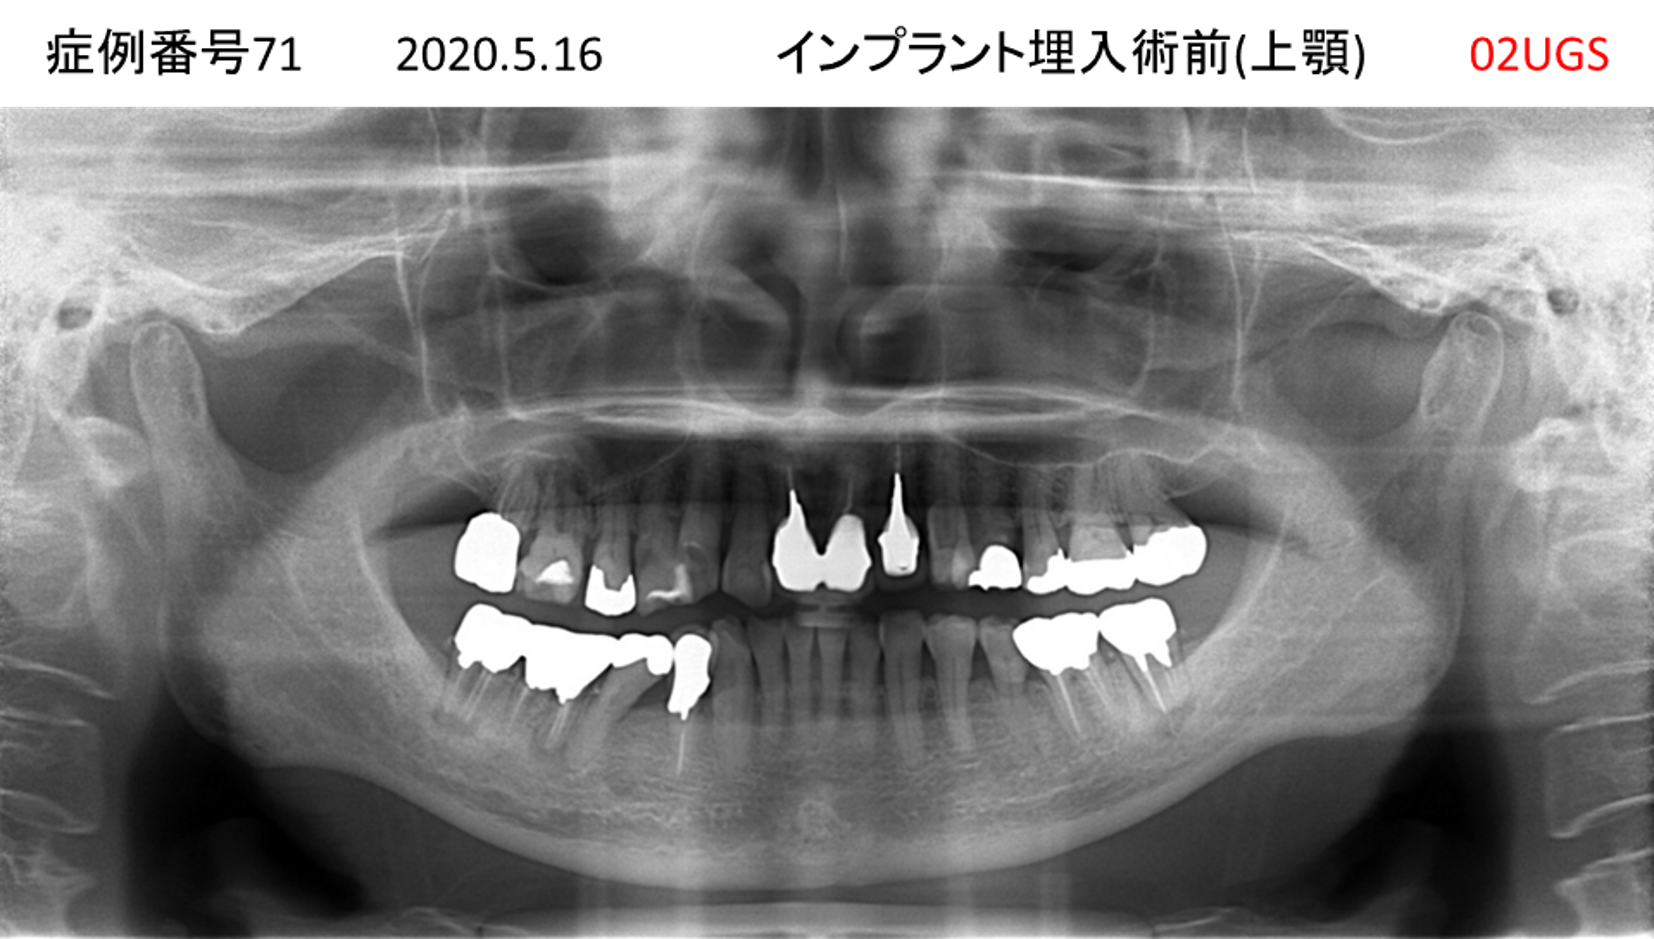

上の前歯が揺れてきてかめない患者様のインプラント症例

| 治療名称 |

インプラント |

| 治療費用 |

440万円+税 |

| 治療期間 |

6か月 |

| 患者さんの症状(主訴) |

上の前歯が揺れてきた。かめない |

| 治療内容 |

サイナスリフト、GBR、インプラント、即時荷重 |

| 治療結果 |

上の前歯の揺れが収まった。奥歯でしっかり噛める。 |

| 治療の注意点(リスク/副作用) |

インプラントが壊れたら再治療が必要 |